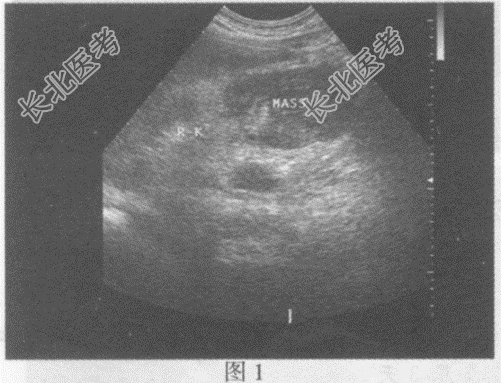

右肾静脉、下腔静脉肝后段管腔增宽,内可见中等回声(图2、图3), CDFI:该段内血流信号充盈缺损。